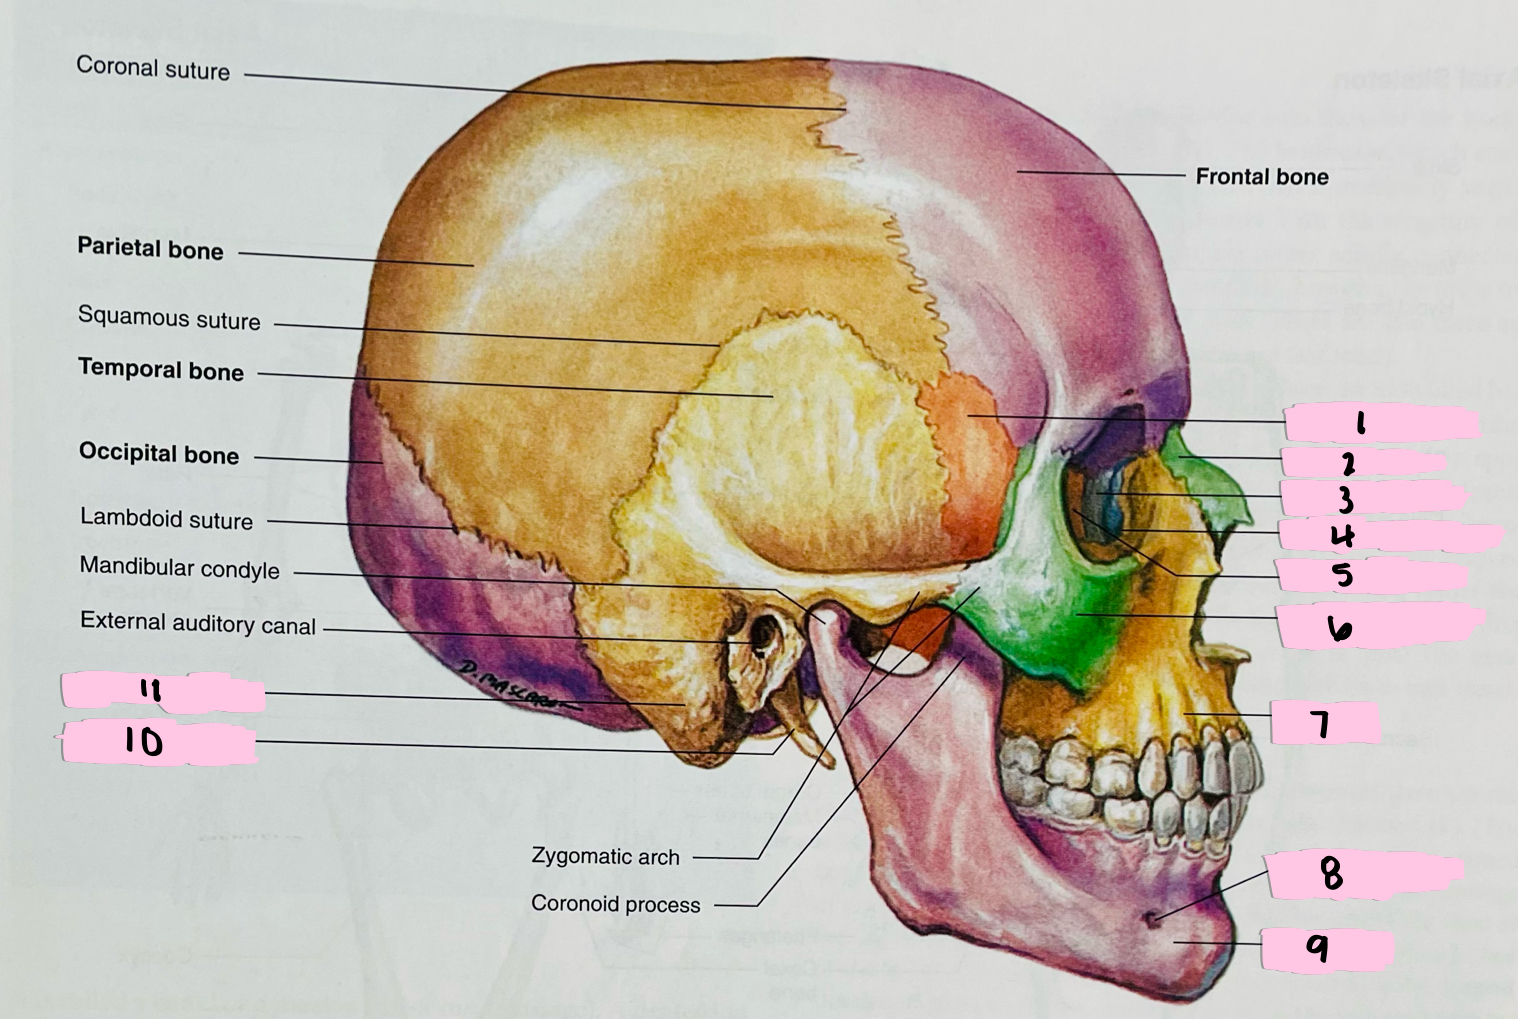

What is 1 pointing to?

Sphenoid bone

What is 2 pointing to?

Nasal bone

What is 3 pointing to?

Lacrimal bone

What is 4 pointing to?

Nasolacrimal canal

What is 5 pointing to?

Ethmoid bone

What is 6 pointing to?

Zygomatic bone

What is 7 pointing to?

Maxilla

What is 8 pointing to?

Mental foramen

What is 9 pointing to?

Mandible

What is 10 pointing to?

Styloid process

What is 11 pointing to?

Mastoid process